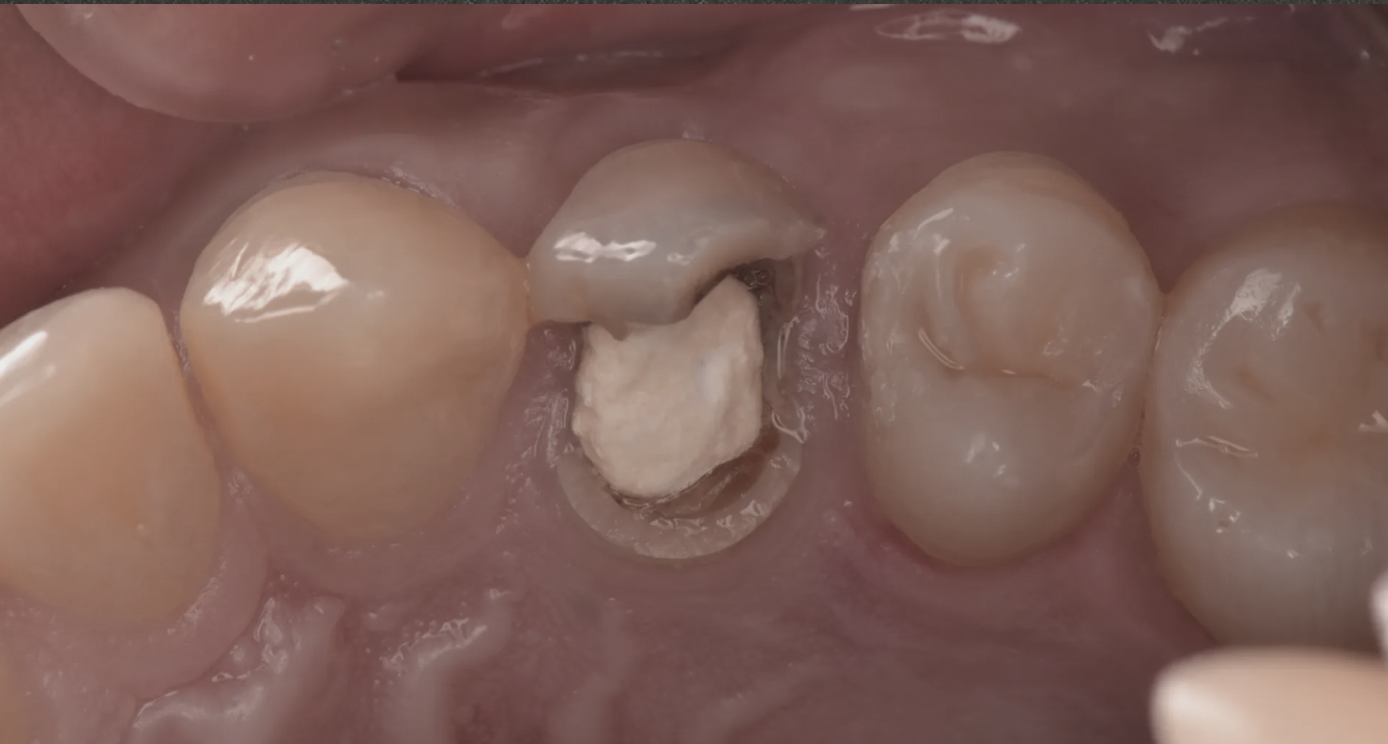

用陶瓷嵌體保住一顆原本被建議拔除的牙

一位後牙因為大面積補牙反覆崩落來找我的病人。一般做法是拔掉做植牙,但我評估後齒質還夠——使用陶瓷嵌體重建,比樹脂耐用、比牙冠保留更多齒質。

能嵌就不冠,能冠就不拔。